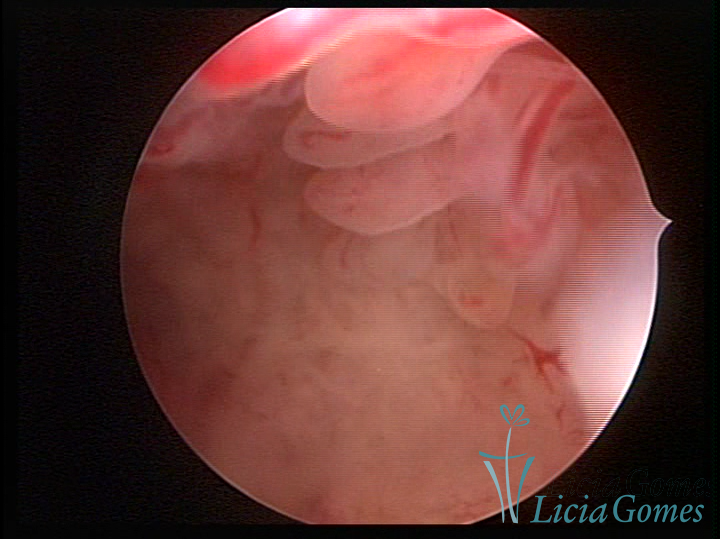

Este pode apresentar uma gama variável de aspectos macroscópicos, com aspecto pseudopolipoide; lembrando tecido cerebroide ou com reação deciduoide;a vascularização superficial é mais evidente e com vasos em formatos de saca-rolha ou espirais visualizando também a vascularização com atípias, com aumento do calibre dos vasos superficiais, pode ser encontrado também tecido em necrose, poderá haver um pequenos dendritos (papilomatoso).